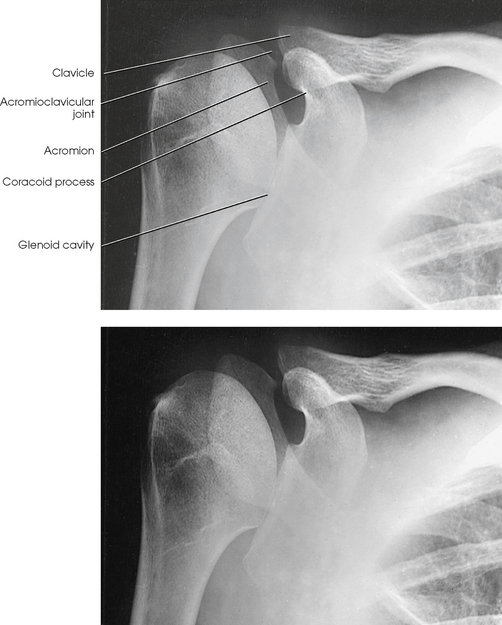

Structures shown: The image shows the bony and soft structures of the shoulder and proximal humerus in the anatomic position (Figs. 5-14 to 5-16). The scapulohumeral joint relationship is seen.

Fig. 5-14 A, AP shoulder, external rotation humerus: greater tubercle in profile (arrow). B, AP shoulder, neutral rotation humerus: greater tubercle (arrow).

External rotation: The greater tubercle of the humerus and the site of insertion of the supraspinatus tendon are visualized (see Fig. 5-14, A).

Neutral rotation: The posterior part of the supraspinatus insertion, which sometimes profiles small calcific deposits not otherwise visualized (see Fig. 5-14, B), is seen.

Internal rotation: The proximal humerus is seen in a true lateral position. When the arm can be abducted enough to clear the lesser tubercle of the head of the scapula, a profile image of the site of the insertion of the subscapular tendon is seen (see Fig. 5-15).